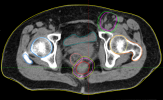

病例展示二:前列腺癌

XXX,男,64岁,主诉:间断性会阴部疼痛10月,确诊为前列腺癌7月。盆腔核磁:前列腺偏左侧异常强化占位,多考虑前列腺Ca,并左侧精囊腺受侵可能,盆腔左侧略大淋巴结。前列腺癌标志物提示:TPSA 88.67 ng/ml,FPSA 3.84 ng/ml。病检:(前列腺穿刺组织左侧)前列腺腺泡腺癌,Gleason评分4+3=7分;(前列腺穿刺组织右侧)Gleason评分3+3=6分。诊断:1、前列腺恶性肿瘤 双侧 腺泡腺癌Gleason评分4+3 =7分 cT3bN0M0 III期 KPS评分:80分。治疗方案:醋酸戈舍瑞林缓释植入剂 10.8mg 皮下注射、比卡鲁胺胶囊 50mg 口服 1次/天”全身治疗,并行前列腺癌碳离子治疗,剂量:57.6 Gy(RBE)/16 Fx。